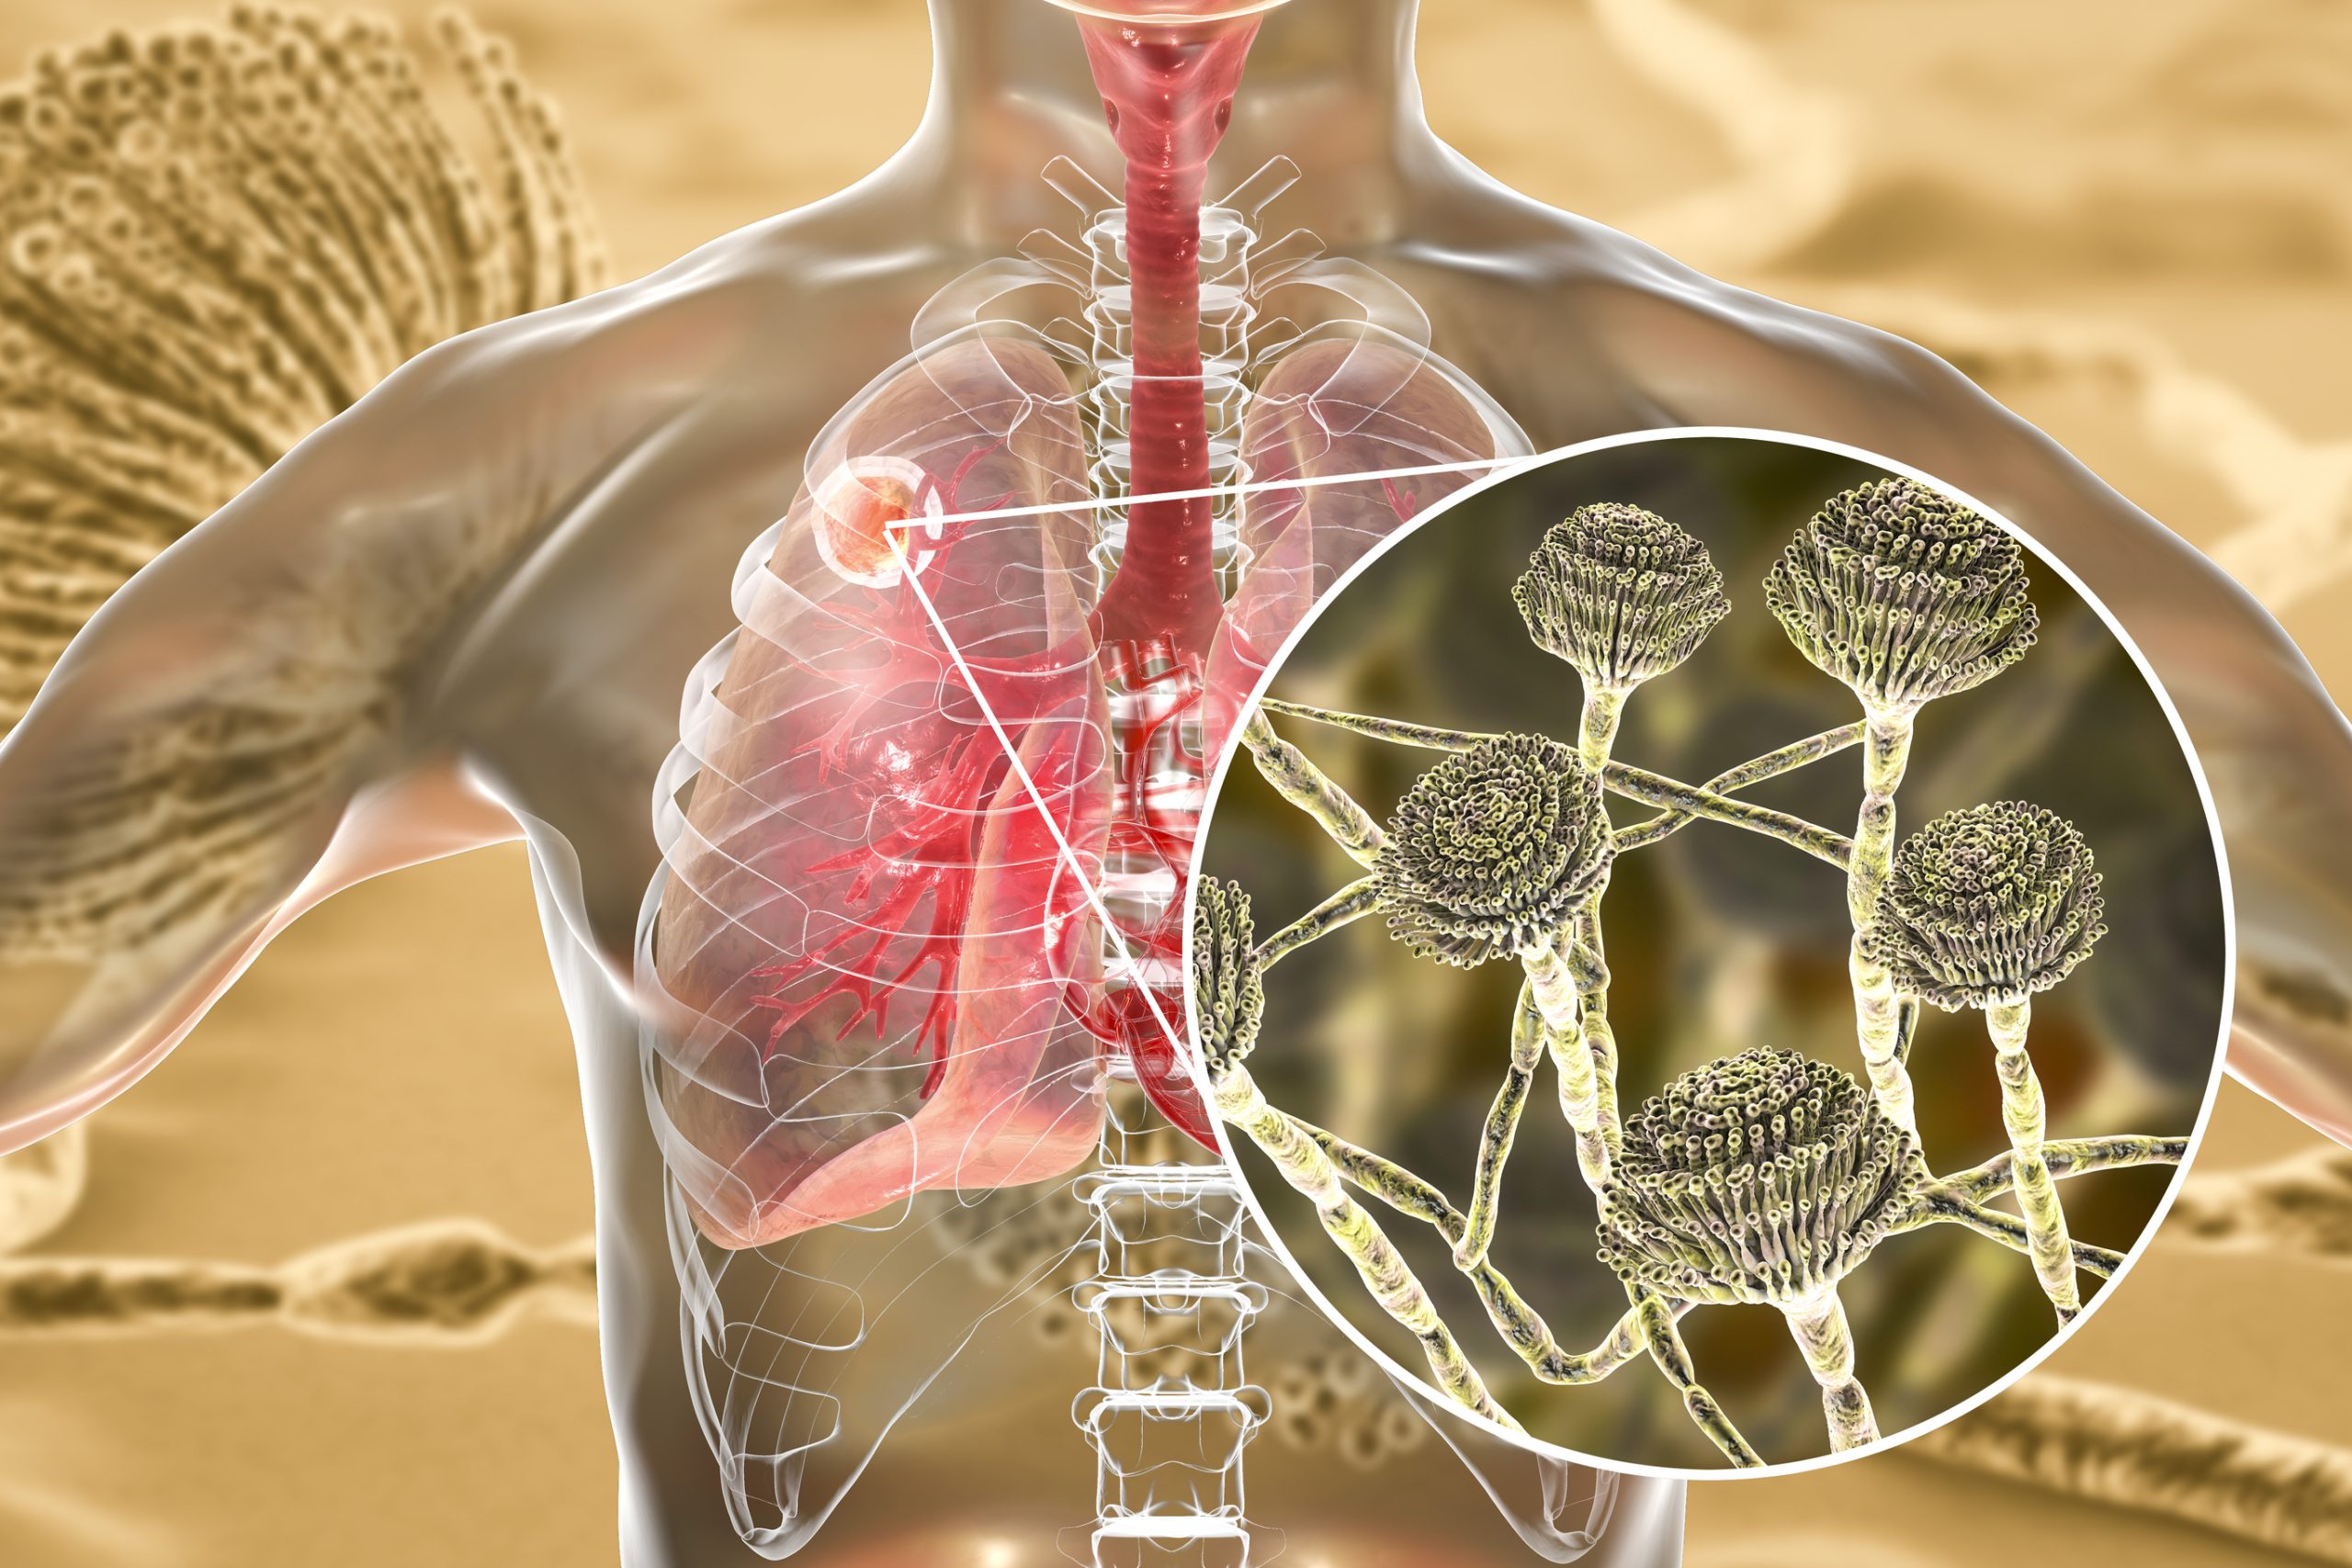

Η ιστοπλάσμωση είναι μια λοίμωξη που προκαλείται από την εισπνοή σπόρων του μύκητα Histoplasma capsulatum, που βρίσκονται συχνά σε περιττώματα πτηνών και νυχτερίδων. Οι άνθρωποι συνήθως νοσούν από την εισπνοή αυτών των σπόρων, όταν μεταφέρονται στον αέρα κατά τη διάρκεια έργων κατεδάφισης ή καθαρισμού.

Ιστοπλάσμωση: Αιτίες

Προκαλείται από τα αναπαραγωγικά κύτταρα (σπόρια) του μύκητα Histoplasma capsulatum. Αυτά επιπλέουν για αρκετή ώρα στον αέρα, όταν υπάρχει ανατάραξη/διαταραχή βρωμιάς ή άλλου υλικού.

Ο μύκητας ευδοκιμεί σε υγρό έδαφος που είναι πλούσιο σε οργανικά υλικά, ειδικά αν πρόκειται για περιττώματα από πουλιά και νυχτερίδες. Είναι ιδιαίτερα κοινός μύκητας σε κοτέτσια και περιστερώνες, παλιούς αχυρώνες, σπηλιές και πάρκα.

ιστοπλάσμωση

Αξονική τομογραφία θώρακος που δείχνει πολλαπλές μικρές βλάβες, συμβατές με πνευμονική ιστοπλάσμωση